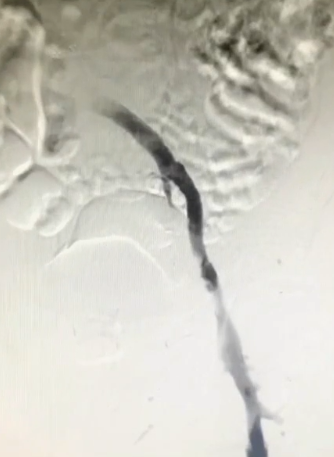

手术过程(二):8F鞘穿刺左侧腘静脉,造影见股浅静脉内充盈缺损,血液回流速度慢,髂外静脉内大量充盈缺损,髂总静脉未见显影,周围侧支循环开放。

手术过程(三):导丝通过髂总静脉略有阻力,交换stiff导丝后,引入DVT血栓抽吸导管,连接AngioJet血栓抽吸装置,于髂股静脉处喷射配置好的20万IU尿激酶,20分钟后,再次引入导管,改为抽吸模式,在髂股静脉血栓内抽吸,部分团块较大的血栓往返抽吸数次。

手术过程(四):退出抽吸导管后,复查造影,股浅静脉内血栓消失,但血流速度仍缓慢,提示近心端仍有梗阻。使用高压球囊扩张髂静脉,可见髂总静脉明显狭窄。分段扩张完成后,引入12 mm×40 mm球囊继续扩张。